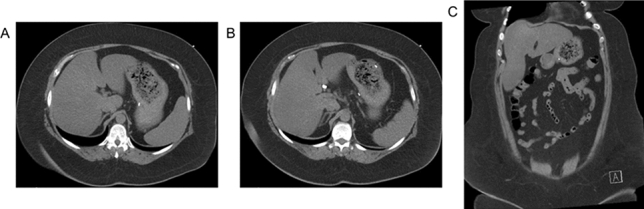

Fig. 1 Hernia sac measurements for calculating VIH (Left to right: axial, sagittal, coronal)